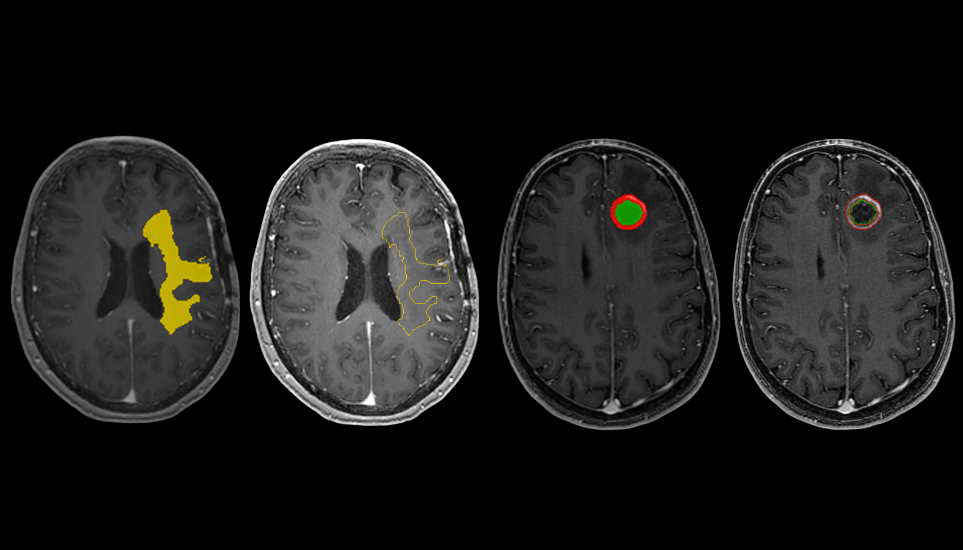

In the realm of neuro-oncology, precision is everything. From diagnosis to treatment planning, clinicians rely on detailed imaging data to make informed decisions that can significantly impact patient outcomes. One of the most critical components in this workflow is the RT STRUCT image, a specialized DICOM format that encapsulates anatomical contours used in radiation therapy planning. Automating the generation of RT STRUCT images with NeuroQuant Brain Tumor can streamline workflows and elevate the standard of care.Cortechs.ai | Enhancing Brain Tumor Treatment with RT STRUCT Images: The Promise of Automation

In brain tumor cases, RT STRUCT images help radiation oncologists precisely define the tumor boundaries and surrounding healthy tissue, ensuring that radiation is delivered accurately while minimizing damage to critical structures.

NeuroQuant Brain Tumor offers a powerful solution: automated segmentation of brain tumors and key anatomical structures from MRI scans. By integrating RT STRUCT export capabilities, NeuroQuant can:

• Automatically generate RT STRUCT files with precise contours of tumors and surrounding anatomy.